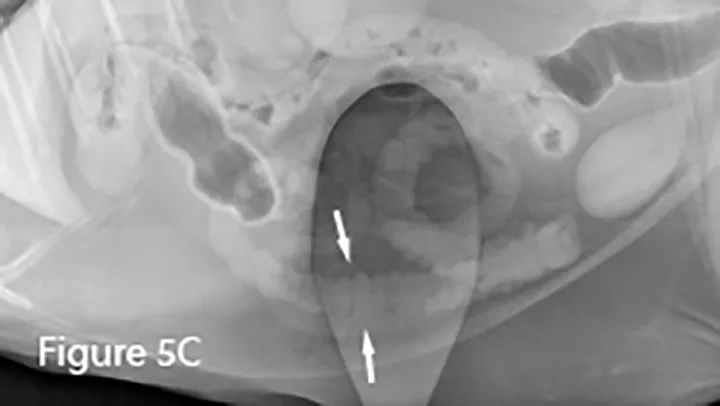

Lateral (Figure 6B) and ventrodorsal (Figure 6C) abdominal radiographs of severely distended segment of bowel identified sonographically and properly diagnosed as severe small intestinal obstruction (arrows). Of note, there is fecal-like material in the small intestine. An ileocecocolic mass was diagnosed during exploratory laparotomy. This mass was apparently obscured by gas during ultrasound examination. (C = colon)